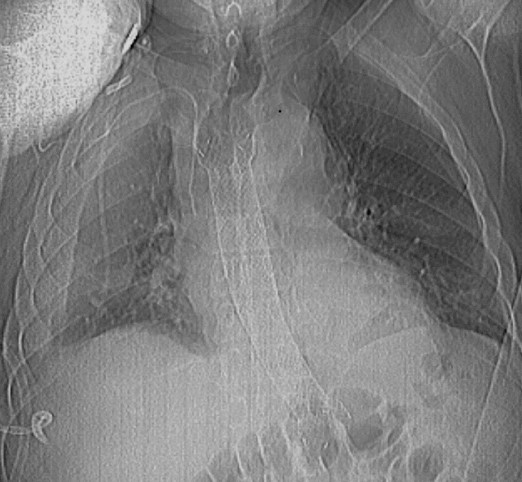

Άνω γαστρεντερική ενδοσκόπηση. Διάτρηση οισοφάγου (Ευγενική παραχώρηση Dr. V. Penopoulos)